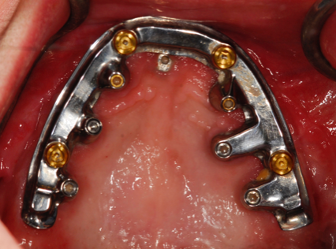

Patient Factors that May Contraindicate Fixed Implant-supported Prosthetics

At the initial patient examination, several factors in addition to restoration shape should be considered when planning implant-supported restorations. History of periodontal disease, irregular maintenance visits, clinical appearance of the remaining teeth and soft tissue conditions may indicate increased risk of peri-implantitis. Patient dexterity, adaptability, willingness, and capability to carry out intended home care should be considered. Patient's mental conditions including dementia may influence the design of this as well as unrealistic patient expectations. A "High water original Branemark design" or no treatment may be indicated. Especially when implant location makes access, a fixed-removable design may be necessary to reduce risk of peri-implantitis may be indicated (Figures 42 through Figure 45). Considering that oral biofilm accumulation, even at two weeks post prosthetic insertion is documented, periodic removal of screw retained restorations is less effective than daily access to disrupt bacterial plaque accumulation.

(42.) Fixed-removable prosthesis.

Figure 42

(43.) Fixed-removable prosthesis.

Figure 43

(44.) Fixed-removable prosthesis.

Figure 44

(45.) Fixed-removable prosthesis.

Figure 45